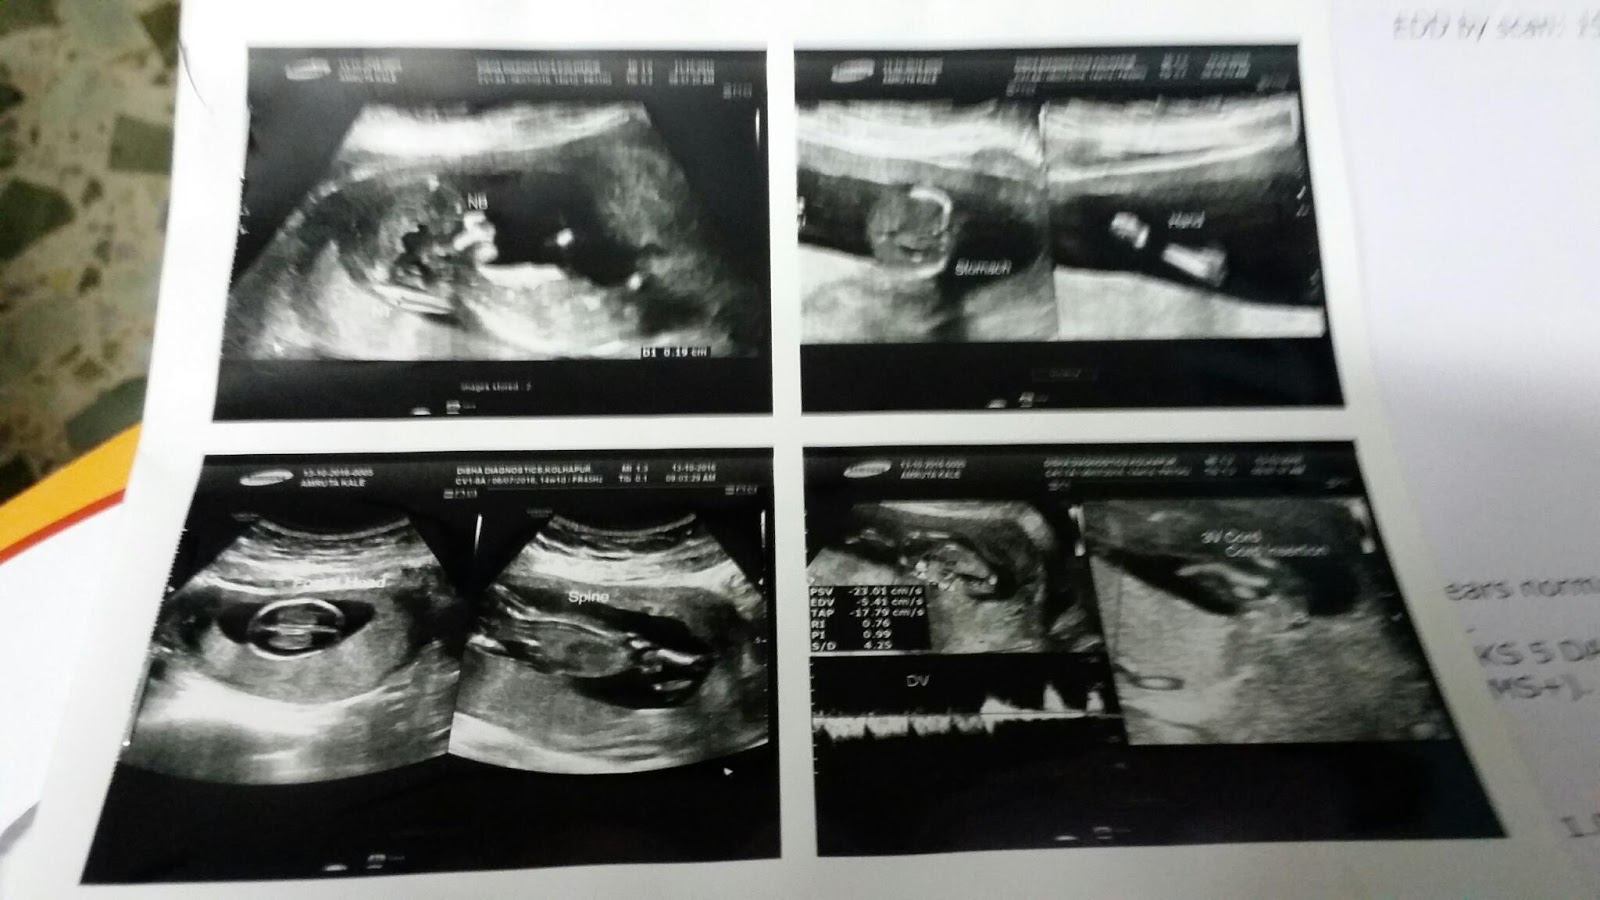

4 months completed

4 month completed to our baby 😙😙